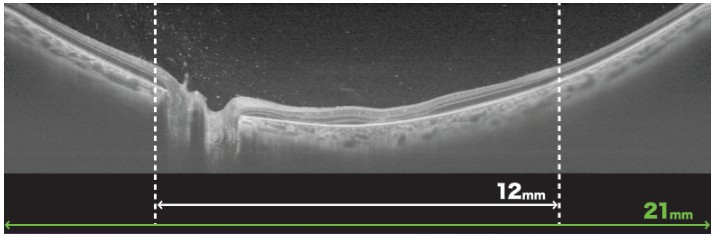

三次元画像解析装置 Triton Plus Pro(Topcon)

三次元画像解析装置(OCT)は現代の眼科に必要不可欠な機器の一つで、主に網膜の層構造を詳細に可視化することで、多くの網膜病変の発見や評価、また治療効果の判定などが的確に行えるようになりました。また視神経乳頭周囲の神経線維の厚さを解析することで緑内障の評価が可能となったり、Angiographyといって網膜血管や脈絡膜血管の血流を造影剤を用いることなく評価することができ、低侵襲で眼底の状態を把握することができるようになりました。 Triton Plus ProはTopcon社が提供する最新鋭のOCTで、眼科臨床で必要とされるすべての機能を高いレベルで可視化することができ、従来機器では評価が難しかった硝子体や網膜、脈絡膜までも鮮明に描写されるようになりました。